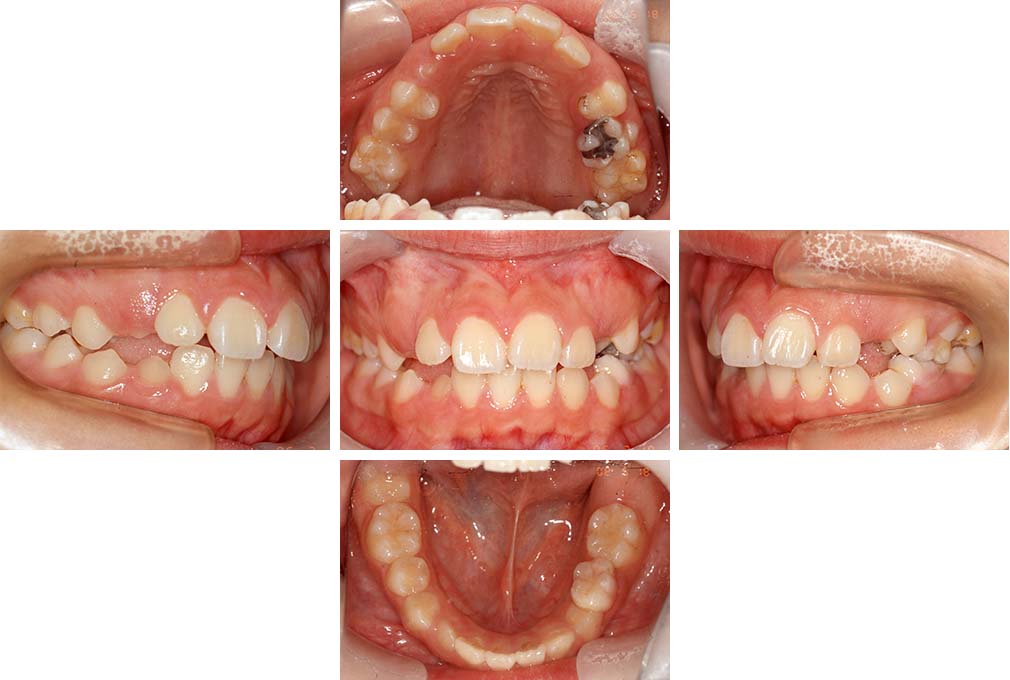

CASE:04

アングルⅢ級傾向を持つ叢生

初診時年齢 22歳

性別 女性

治療費の目安 105万円程度(治療開始時)

上顎右側犬歯が唇側に転位していることを主訴に県内歯科医院から紹介来院された。骨格的にはⅢ級傾向で上顎右側犬歯が唇側転位となり、側切歯が口蓋側に転位していた。下顎前歯が叢生になっていることも相まって上下の正中線は右側に大きくずれていた。アングルⅢ級傾向を持つ上下顎前歯部叢生と診断した。

上下顎小臼歯を抜歯していただき上顎舌側、下顎唇側マルチブラケット装置を使用して動的治療を行った。矯正用ゴムの使用など協力状態も良く、正中線の大きな移動があったのも関わらず2年10カ月で装置を撤去し保定へ移行した。保定移行後14年が経過し、ご息女の診察でご来院いただいていたことから、口腔内を拝見したが、下顎前歯のわずかなずれがあったものの大きな歯列の乱れはなく歯列は安定していた。動的治療期間2年10カ月間。

治療前

22歳6か月

治療後

動的治療期間2年10カ月間

25歳6か月

治療終了

動的治療終了後2年2カ月

28歳8か月

14年経過

動的治療終了後14年7カ月

40歳1か月